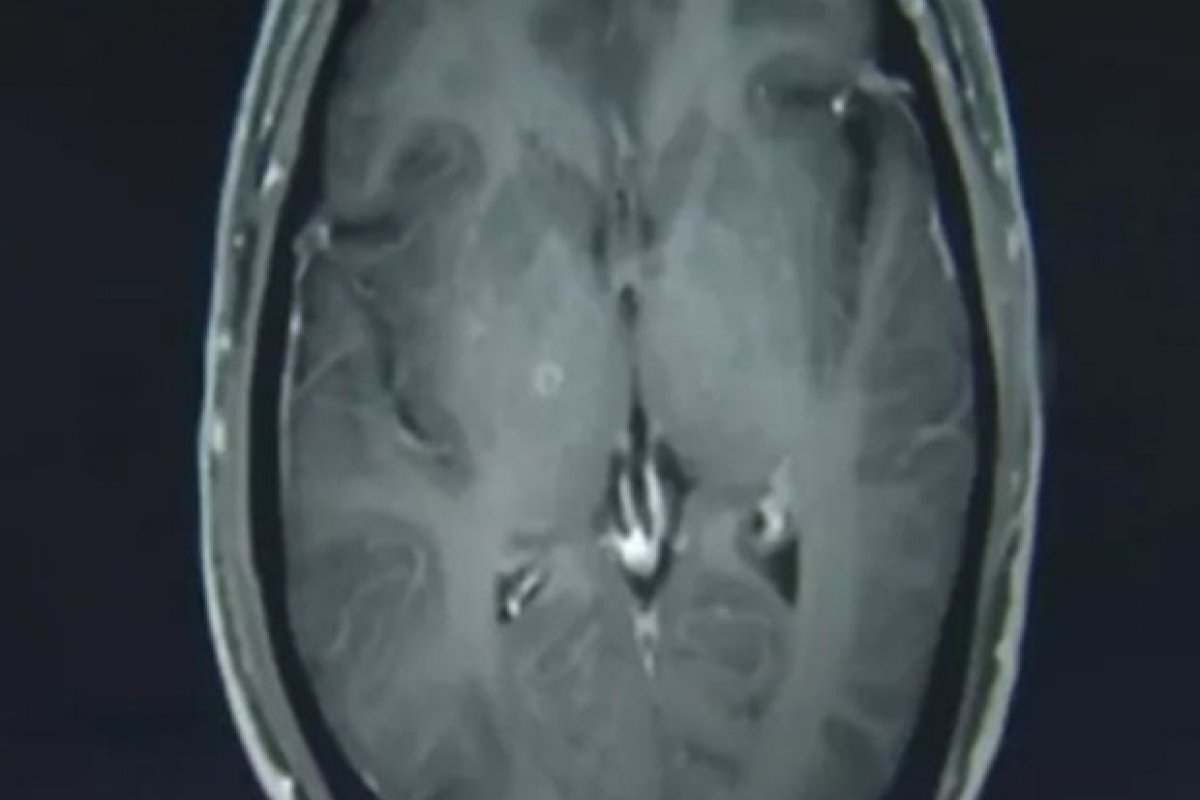

Foto: Reprodução/Hospital da Universidade de Zhejiang

Zhu Zhongfa foi parar no Hospital da Universidade de Zhejiang, no leste da China, apresentando graves convulsões, que se assemelhavam a um quadro de epilepsia. Quando foi realizado o exame de ressonância magnética, os médicos se espantaram com o resultado. Analisando as imagens do cérebro de Zhu, os profissionais perceberam centenas de calcificações e lesões no órgão.